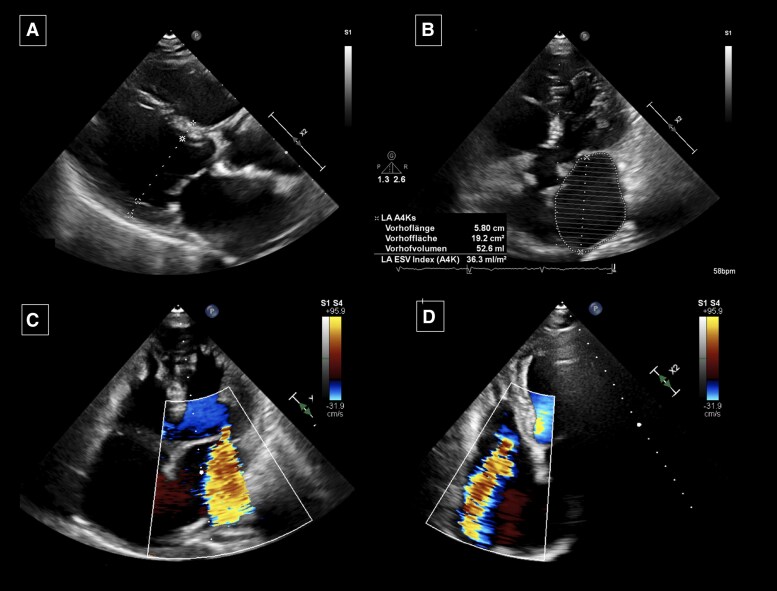

Case summary: We describe a case of an 86-year-old female with a history of AF and previous pulmonary vein isolation presenting with symptoms of acutely decompensated heart failure and recurrence of atrial flutter. Her echocardiography demonstrated non-dilated left ventricle with a normal ejection fraction, left atrial (LA) dilatation, severe FMR, and tricuspid regurgitation (TR). Due to failed electrical cardioversion and amiodarone intolerance, a successful catheter ablation of a LA flutter was performed. Electro-anatomical mapping revealed extensive LA low-voltage areas. During the follow-up of 18 months, the patient remained in sinus rhythm, and the FMR improved to MR II (effective regurgitant orifice area of 9 mm2 and regurgitant volume of 18 mL); no improvement of the TR occurred.